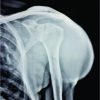

The radiographs of all the hips showed healing of the drill tracts, well-contoured femoral heads, and no signs of stage progression or collapse at last follow-up at 1 year (Fig. 2,3,4).